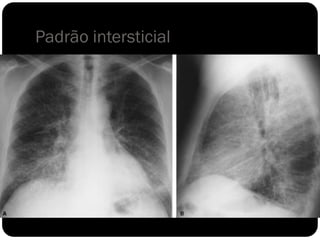

Padrão intersticial

 O interstício pulmonar é todo o tecido conjuntivo de

sustentação que mantém a arquitetura alveolar. Os vasos,

brônquios e linfáticos situam-se no interstício.

 Infiltrações intersticiais parenquimatosas podem aparecer na

forma de padrão

reticular

micronodular

reticulonodular.